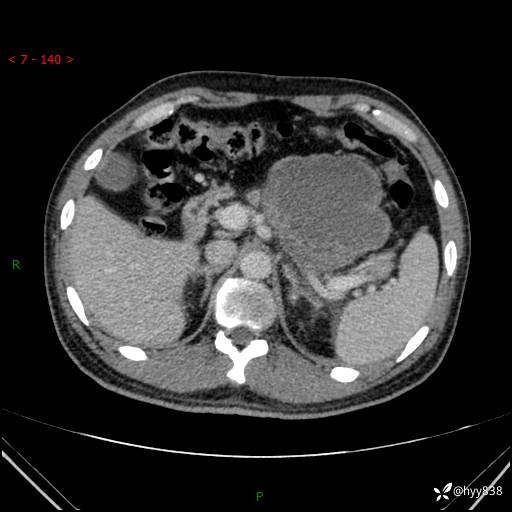

病例39岁/女,左侧腰痛入院。腹腔囊实性肿块,定位、定性---结果公布~

性别:男

年龄:39岁

简要病史:左侧腰痛待查,CT发现腹腔占位

腹部CT平扫+增强